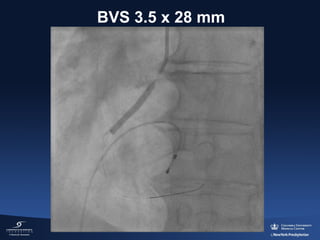

BVS 3.5 x 28 mm

Post-dilation NC 4.0

“Juxtaposition” of 2 BVS:

0.2 mm gap at OCT measurement